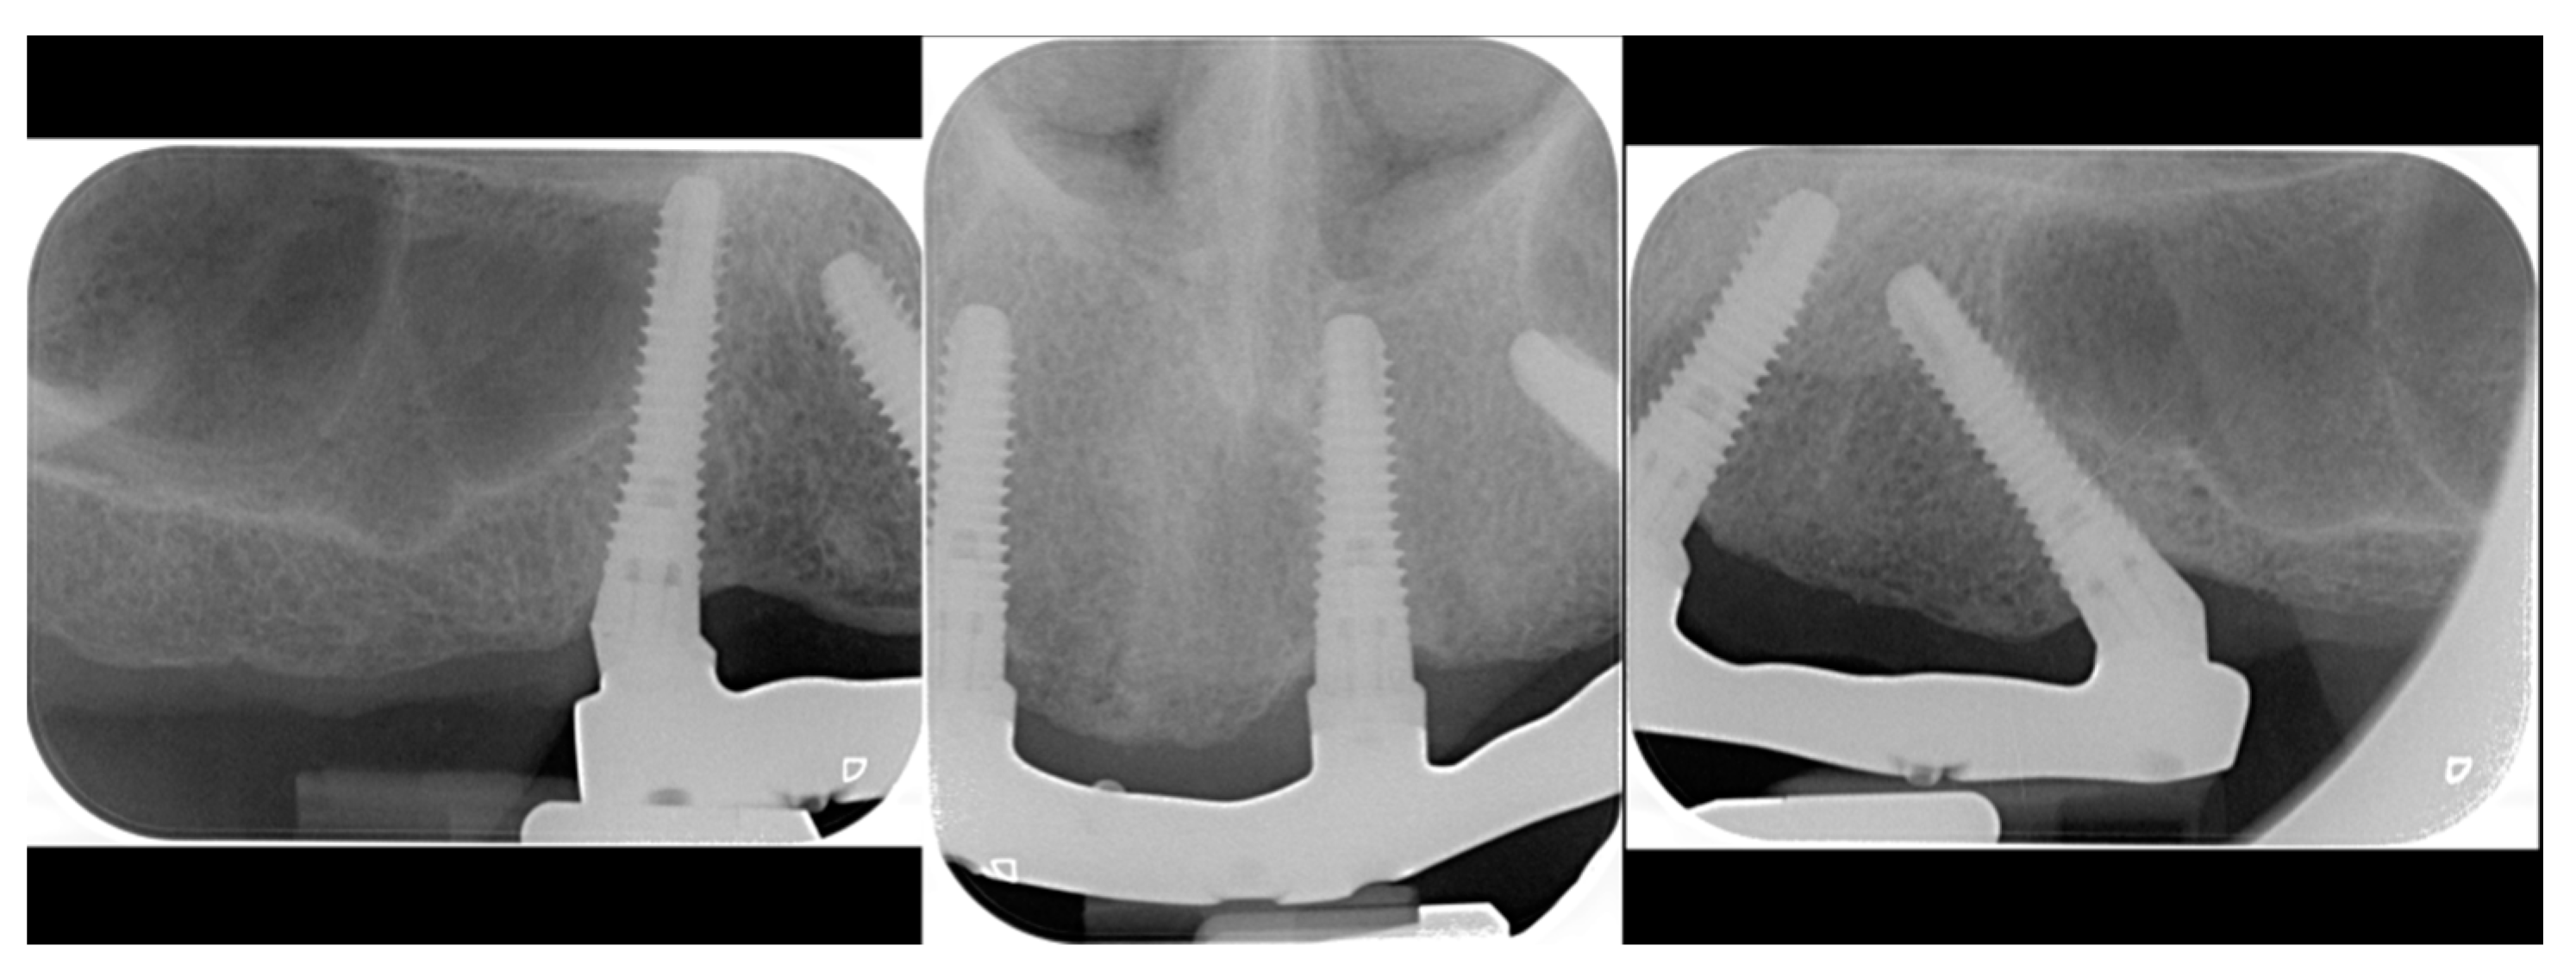

2.1. First Step: Complete Fixed Rehabilitation

2.2. Second Step: From FDP to Implant-Supported Overdenture